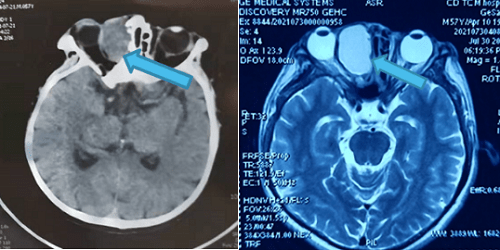

患者格某 , 男 , 今年57岁 , 因发现右眼眶包块10余天 , 压迫眼球 , 多方求医无果 , 遂到成都爱尔眼科医院寻求诊疗 。 经过CT及MRI检查影像显示 , 眼眶肿物与筛窦相通 , 局部骨质缺损 , 眼球受压变形 , 如不及时治疗 , 将严重影响右眼的功能 。